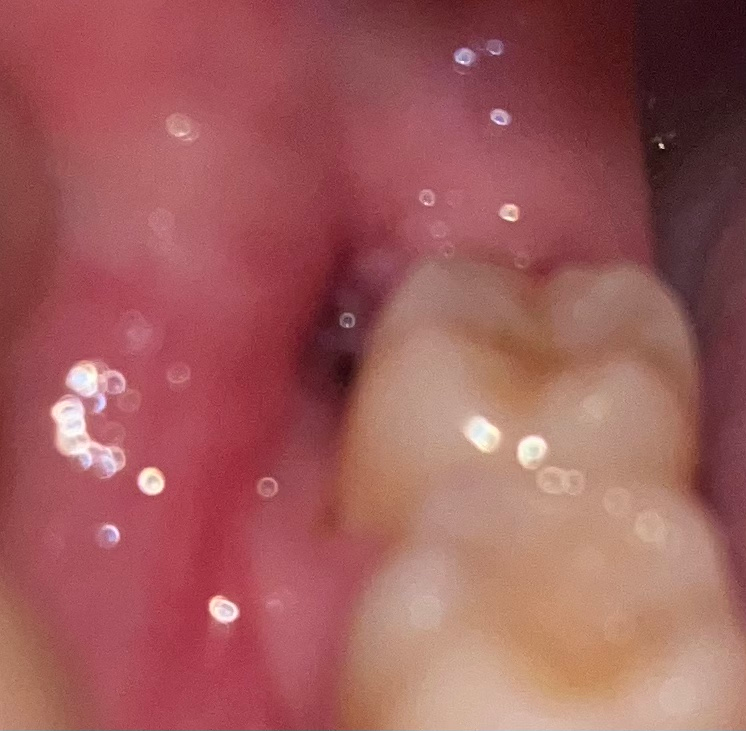

사랑니 발치후 발치와가 완전히 아무는데는 한달에서 두달정도 소요되실꺼에요. 그때까지 음식물이 낄수 잇으니 식사를 하시고 물로 여러번 헹구시는게 좋습니다.

발치부위는 1달 정도 지나면 살이 차오릅니다..발치부위에 들어간 음식물은 물로 헹궈서 빼주고..제거가 안되면 워터픽이나 바늘없는 주사기의 압력으로 제거 합니다.